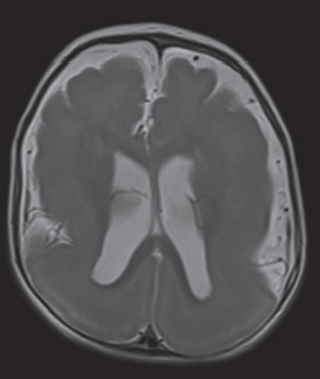

La resonancia magnética cerebral permitió reconocer un engrosamiento difuso de la corteza cerebral de forma bilateral con disminución de la superficie giral suprayacente, así como apariencia lisa de ambos hemisferios (figura 3), además se asoció con la presencia de heterotopia en banda hiperintensa en T1 e hipointensa en T2 (figura 4), así como disminución generalizada del grosor del cuerpo calloso y de ambos hipocampos (figura 5). Mediante este estudio se brindó el diagnóstico de lisencefalia de tipo 1 con heterotopia en banda del grupo IIB.

Figura 3 Corte axial de resonancia magnética cerebral ponderada en T2 que muestra engrosamiento difuso de la corteza cerebral bilateral y apariencia lisa de la superficie cortical